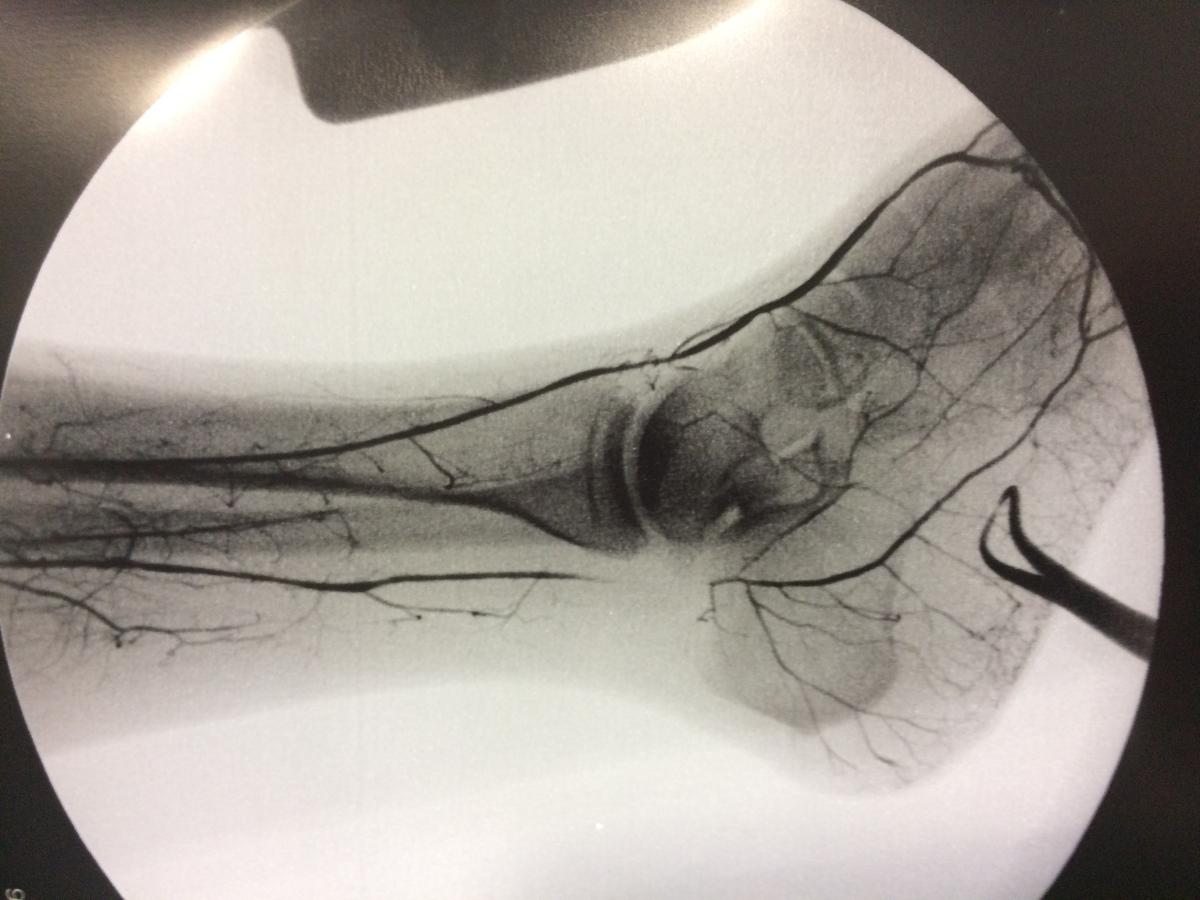

Cirugía Vascular periférica y Endovascular